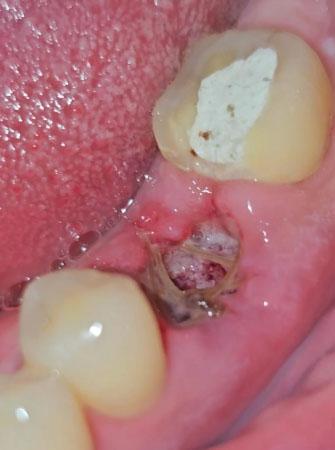

This clinical image shows a localized infection in the lower posterior jaw with an open gum socket and visible exposed bone. The surrounding tissue is inflamed, indicating an active infection that may involve both soft tissue and underlying bone.

Open socket in the molar region

Visible exposed bone inside the socket

Surrounding gum tissue appears red and inflamed

Debris and necrotic tissue present

Adjacent teeth remain structurally intact